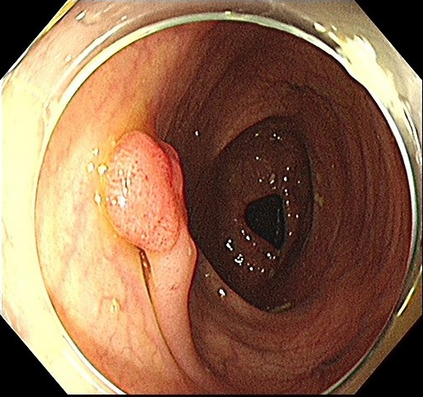

We improved an existing end-to-end polyp detection model with better average precision validated by different data sets with trivial cost on detection speed. Previous work on detecting polyps within colonoscopy \cite{Chen2018} provided an efficient end-to-end solution to alleviate doctor's examination overhead. However, our later experiments found this framework is not as robust as before as the condition of polyp capturing varies. In this work, we conducted several studies on data set, identifying main issues that causes low precision rate in the task of polyp detection. We used an optimized anchor generation methods to get better anchor box shape and more boxes are used for detection as we believe this is necessary for small object detection. A alternative backbone is used to compensate the heavy time cost introduced by dense anchor box regression. With use of the attention gate module, our model can achieve state-of-the-art polyp detection performance while still maintain real-time detection speed.